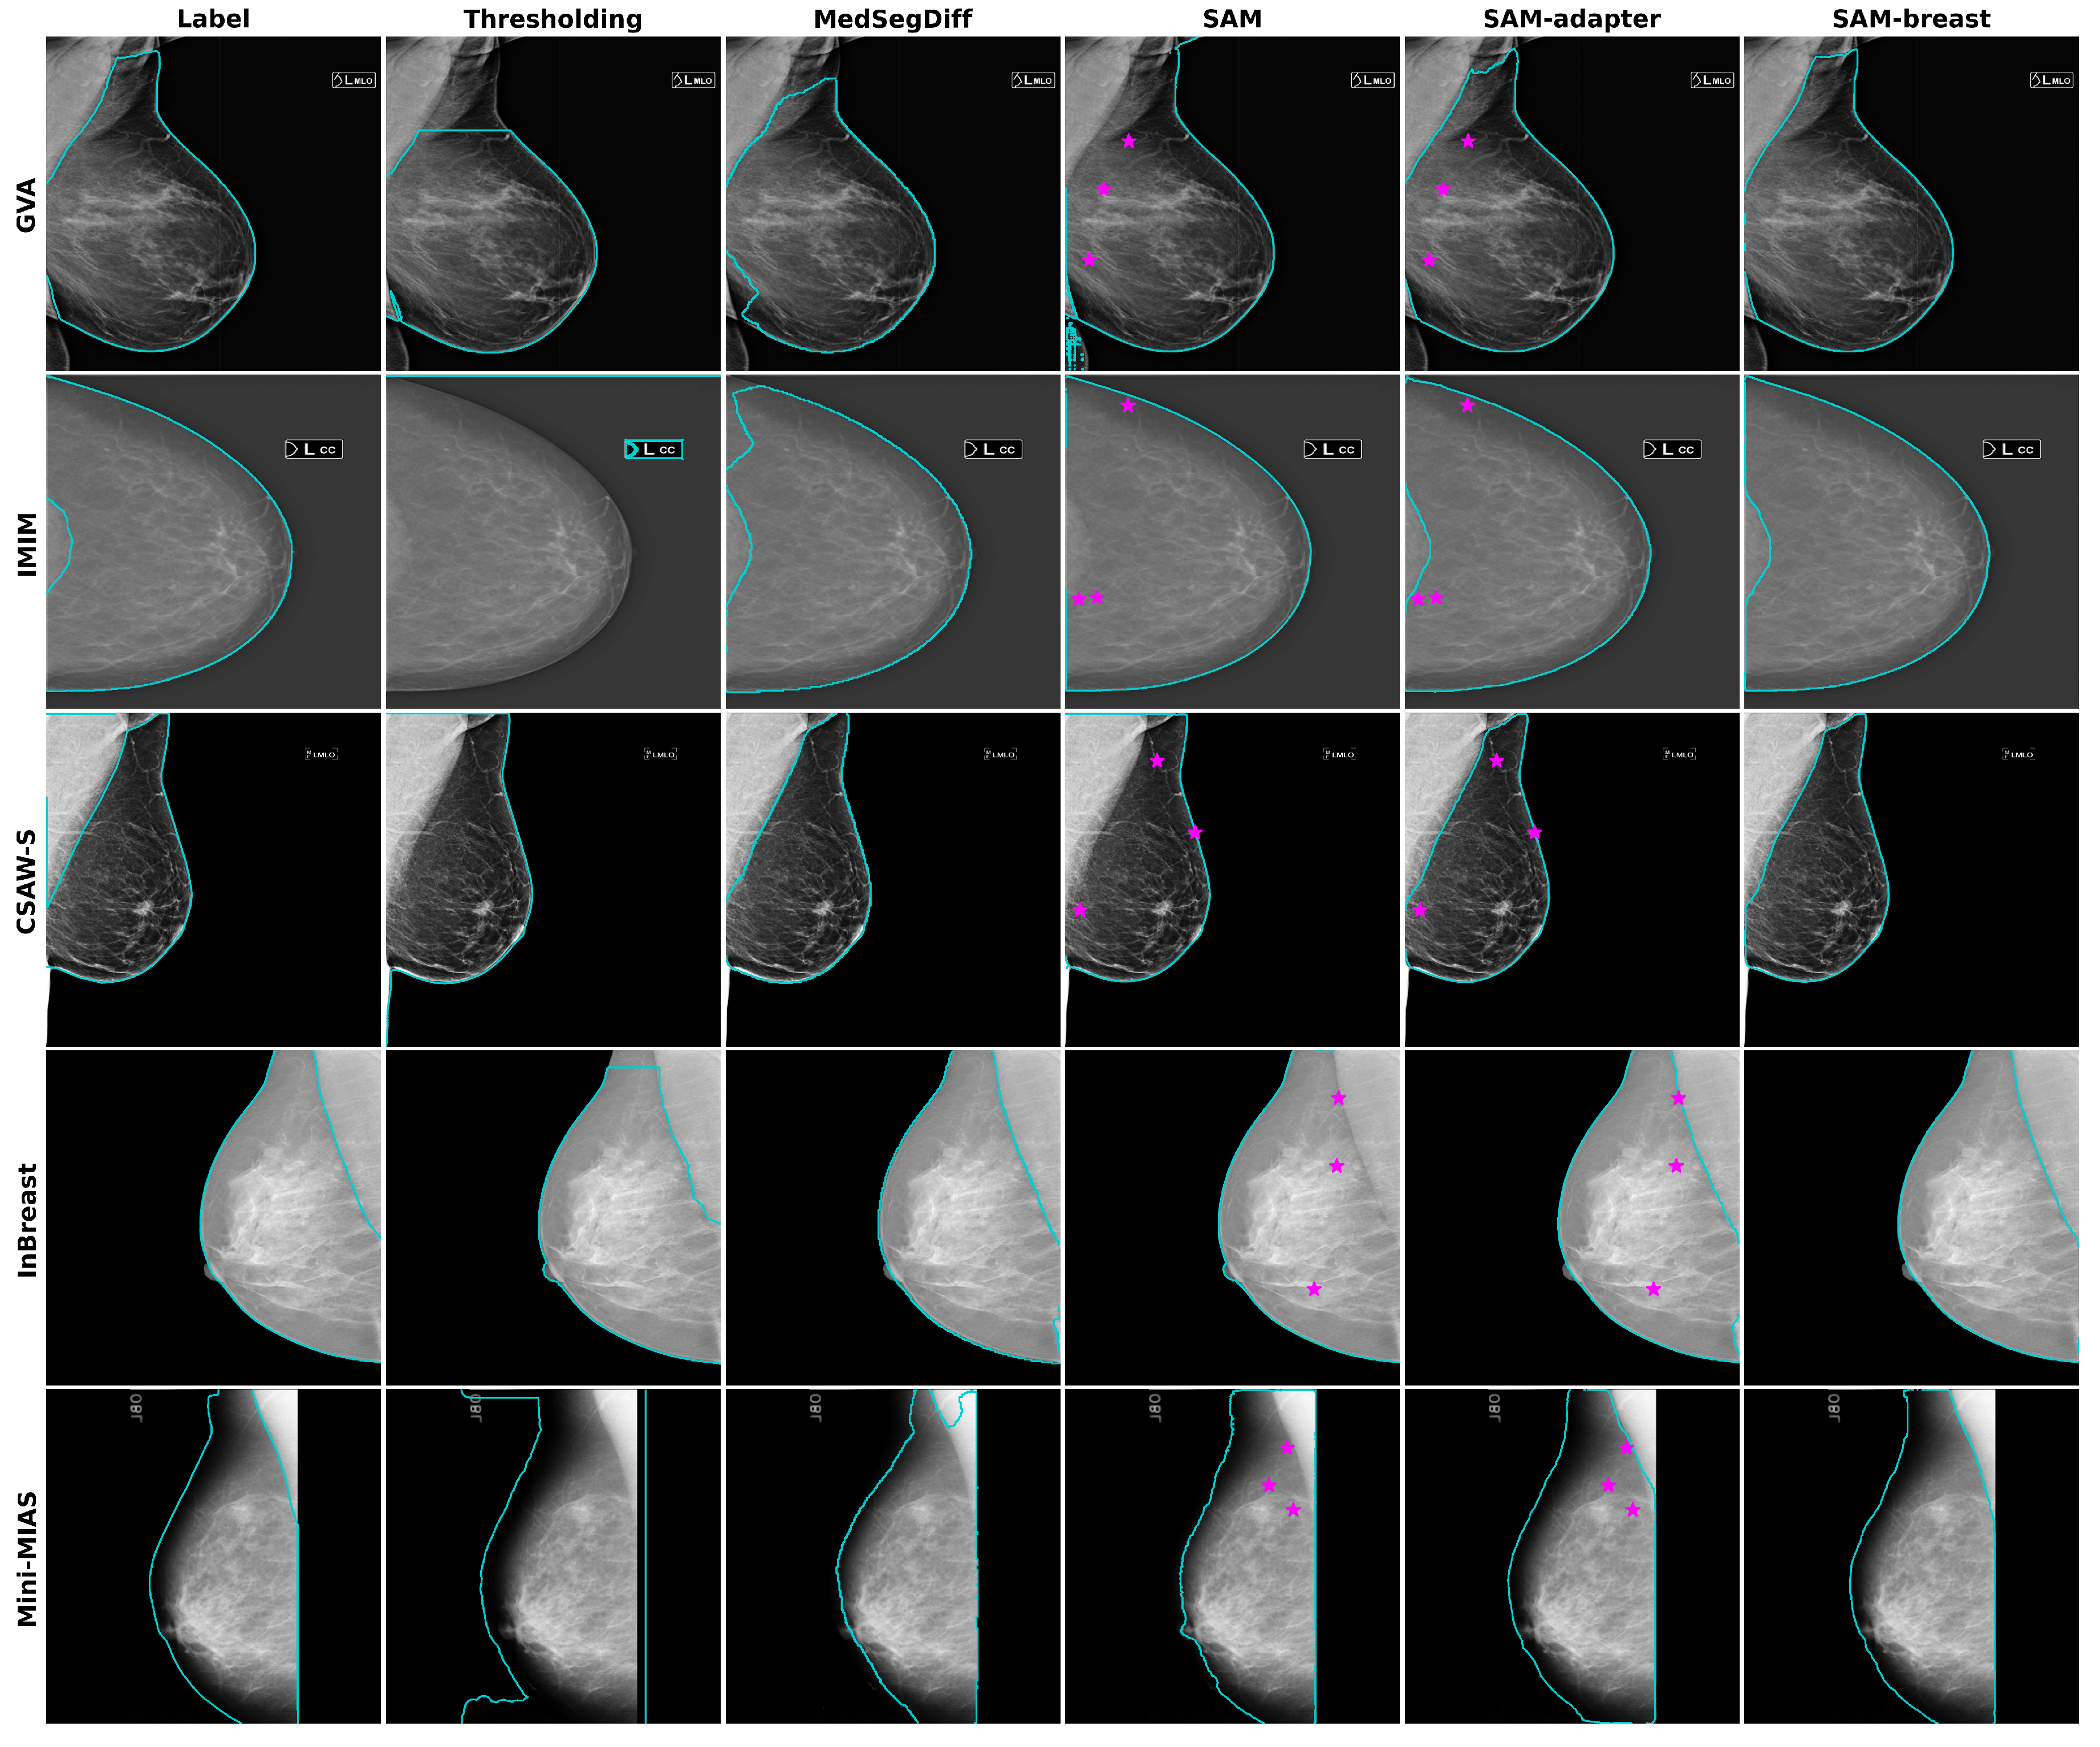

- GVA (proprietary): A multi-center dataset that covers 11 medical centers of the Generalitat Valenciana (GVA) as part of the Spanish breast cancer screening network. It includes 1785 women with ages from 45 to 70. The CC and MLO views were available for 10 out of 11 of the centers, while one center only collected the CC view. This dataset was used for training, validation, and testing. The dataset was randomly partitioned into 75% (2492 mammograms) for training and validation (10%) and 25% for testing (844 mammograms). All the mammograms are of the type “for presentation”. Further details about this dataset can be found in our previous work [9].

- IMIM (proprietary): A dataset composed of 881 images obtained at the Hospital del Mar Research Institute (IMIM). It was included solely for testing purposes to better evaluate the generalization performance of the models. This dataset consists of images from three different acquisition devices. One of these devices (Hologic Lorad Selenia, Marlborough, MA, USA) is older and was used to obtain images back in 2012. As a result, the image quality is lower, making the segmentation task more challenging. Only CC views were provided for this dataset, and they are also of the type “for presentation”.

- CSAW-S (public): The CSAW-S dataset, released by Matsoukas et al. [19], is a companion subset of CSAW [20]. This subset contains mammograms with expert radiologist labels for cancer and complementary labels of breast anatomy made by non-experts. The anonymized dataset contains mammograms from 150 cases of breast cancer, some of them including both MLO and CC views. We generated the breast masks for our experiments by combining the provided mammary gland and pectoral muscle labels, thus obtaining a total of 270 images with breast mask segmentations.

- InBreast (public): A well-known publicly available dataset [21]. It has ground truth annotations for the pectoral muscle in MLO views. We used these annotations to generate the ground truth breast mask for a total of 200 images.

- Mini-MIAS (public): The Mini-MIAS database [22], created by the Mammographic Image Analysis Society (MIAS), is a resource that has been extensively used in prior research. It contains 322 digitized mammographic films in MLO view. The breast masks that we used for evaluation were obtained from Verboom et al. [23].